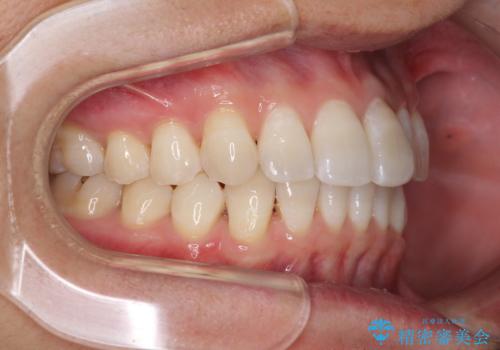

前歯のデコボコを治したい インビザラインによる矯正治療

- 前歯のデコボコを治したいとのことで来院された患者様です。

上下顎ともに歯列全体の後方移動とIPR(歯と歯の間を削る)によってデコボコが解消するように設計し、インビザラインにより治療を行うこととしました。

矯正治療後、前歯の形と色が気になるとのことでしたが、大分前に失活している(神経が取り除かれている)歯であり、その影響で変色しているため、オールセラミッククラウンによる補綴治療をおすすめいたしました。